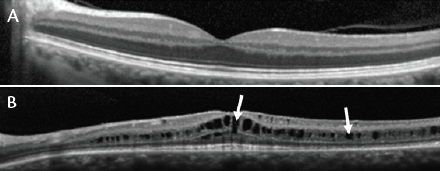

Figure 1. Optical coherence tomography (OCT) scan through the fovea of a normal retina (A). OCT scan through the retina of a patient with XLRS, showing splitting of the layers of the retina (B). White arrows mark cysts that have formed in the fovea (left arrow) and in the macula outside of the fovea (right arrow).

XLRS is an orphan inherited disease of the retina caused by mutations in the RS1 gene, which encodes the retinoschisin protein.3 Retinoschisin is expressed and secreted from photoreceptors and bipolar cells, and it binds strongly and specifically to the surfaces of many cells in the retina.4-6 Mutated forms of retinoschisin are unable to bind properly, which leads to splitting (schisis) of the layers of the retina (Figure 1).